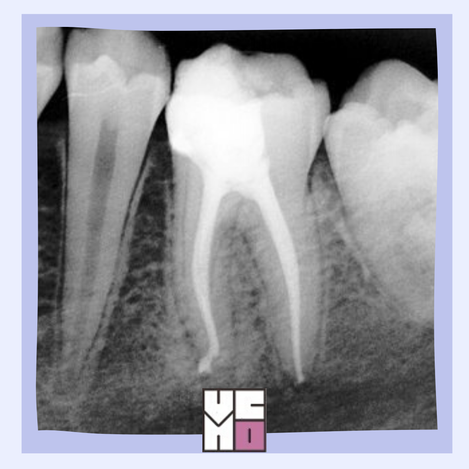

La endodoncia de hoy

Las nuevas tecnologías facilitan la realización y los resultados de los tratamientos de conducto.

La endodoncia

El tratamiento endodóntico o tratamiento de conducto explicado de manera sencilla, para entenderlo mejor y valorarlo.